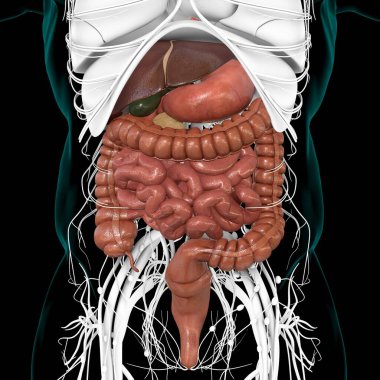

Sindirim Sistemi

En Çok Aranan Kelimeler

MaviresimlemeİnsanKadınSağlıkkanİlaçAğızSolunumerkekkalpgövdeMidebiyolojiBilimSistemözetorgİskeletanatomiKas gücübeyinSistemlersindirimGerginakciğerlerkaraciğerBöbrekiskeletOrganlaranatomikBağırsaklarBağırsakKolondolaşımdalakBenzer İçerikler